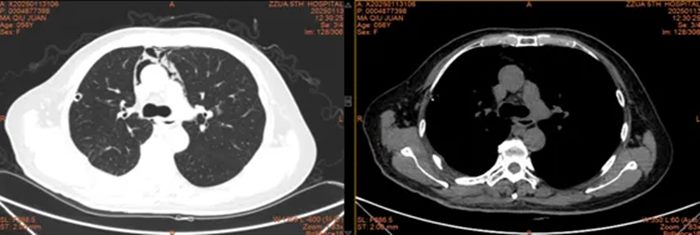

术后CT

患者术后恢复良好,马女士及其家人激动地向高主任表达了深深的谢意。如今,患者现已顺利康复出院,回归正常的生活。